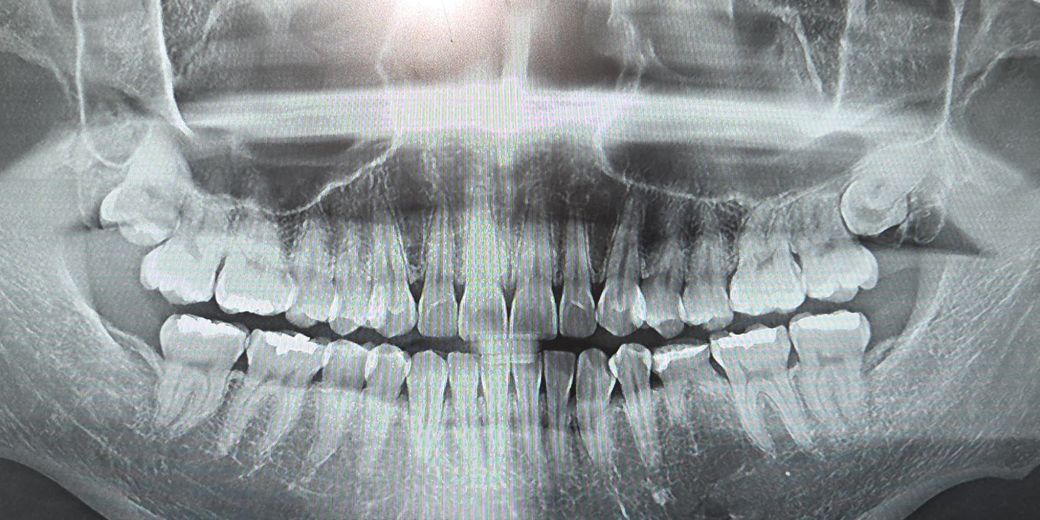

사랑니 뽑았을때 옆 어금니가 위험할까요?

제 친구가 자기는 위쪽 사랑니가 옆 어금니에 너무 가깝다고 뽑으면 어금니도 위험해져서 잘못하면 몇년 내에 어금니도 빠질수 있어서 임플란트를 해야할 수 있다는 말을 들었다고 하더라고요.

근데 그 친구가 화면 기준 오른쪽 위 사랑니처럼 어금니 방향으로 나는 유형이었습니다.

지금까지 의사선생님들 모두 옆 어금니 위험해질거란 말은 하신 적이 없어서 상관없지 않을까 싶긴한데... 친구가 저랑 비슷한거 같아서 괜시리 걱정되네요.

사진기준 바깥방향으로 난 왼쪽 사랑니는 살짝 잇몸을 뚫고 돌출됐고 어금니 방향으로 자란 오른쪽 사랑니는 잇몸 안에 완전히 덮혀있습니다.

1.양쪽 사랑니를 뽑았을때 혹시 옆 어금니에 영향을 줘서 어금니를 약하게 만들어서 위험하게 만들까요?

2.양쪽 사랑니 모두 어금니를 안 건드리고 뽑을 수 있는 사랑니들인가요?

3.사랑니가 뽑히면 그 부분을 뼈메꾸는데 6개월쯤 걸린다는데 그 사이에 어금니가 위험해지는 경우도 있나요?

4. 30 이후에도 사랑니가 계속 자라거나 움직이나요?

사랑니를 꼭 빼야할 필요는 없어보입니다. 어금니가 위험해질 것 같진 않고 계속 움직이지도 않습니다.

위쪽에 잇는 사랑니의 경우는 특별히 불편한거 아니라면 발치를 하지 않으셔도 크게 문제가 될건없을것같습니다. 오히려 발치를 하면 치아 뒤쪽 잇몸뼈가 없어서 관리가 쉽지 않을것같습니다.

사진으로 봤을 경우에 사랑니가 어금니를 약하게 하거나 않을것으로 생각됩니다. 사랑니가 완전히 매복되어 있고 문제를 발생시키지 않는다면 굳이 발치를 할 필요가 없습니다.